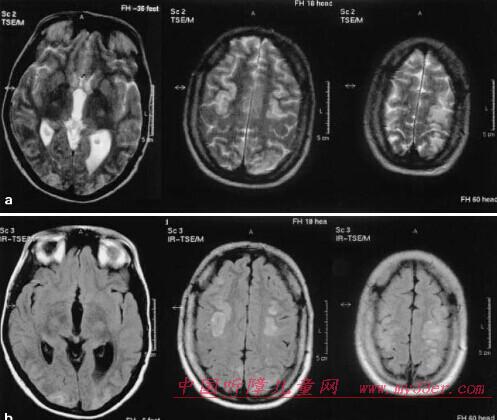

3.1 儿童脑白质病的MR信号改变产生基础 正常脑白质含水量较脑灰质少,而脂质成份较灰质多,因此脑白质容易缩短自旋的纵向弛豫时间,随着脑白质发育的逐渐成熟及髓鞘的形成,在MRI上灰-白质界线逐渐分明,脑白质T1和T2时间逐渐缩短,髓鞘化过程至2岁时脑白质T2时间接近成年人。当髓鞘由于各种原因受到损害时引起自由水增多,髓鞘发生变化,造成T1和T2弛豫时间延长。在MRI上由于T2WI较T1WI更能敏感地显示水含量的变化,因此主要表现为脑白质内T2WI上的高信号改变。

3.2 儿童脑白质病的MRI表现 各种类型的儿童脑白质病在MRI上均可表现为T2WI脑白质内高信号改变。对于脑白质病的显示,MRI明显优于CT。

MRI是显示脑发育过程中脑内各种解剖结构形态变化的最佳影像学手段,显示脑白质髓鞘发育成熟过程也以MRI为首选。在T1加权像上,无髓鞘的脑白质呈低信号,随髓磷脂出现并成熟,脑白质逐渐变为高信号。相反,在T2加权像上,无髓鞘脑白质呈高信号,随髓磷脂成熟,脑白质信号强度逐渐下降。通常,在出生后头6个月~8个月,监测髓磷脂发育,以T1加权像为佳;而出生6个月后,则以T2加权像更为敏感。

3.MRI诊断:MRI是显示脑白质及白质病灶最敏感的方法,以T2加权像更为敏感。除横断位外,还应包括冠状断扫描,有些病理变化仅在冠状断T2加权像上才能充分显示。T2加权像显示的髓磷脂沉积过程与尸检切片髓磷脂染色所见,相关良好。在矢状断像上,MRI可显示脑干脑白质的发育情况。若常规扫描发现脑白质信号异常,可行增强扫描,以确定病灶的严重程度、活动性和进行鉴别诊断。